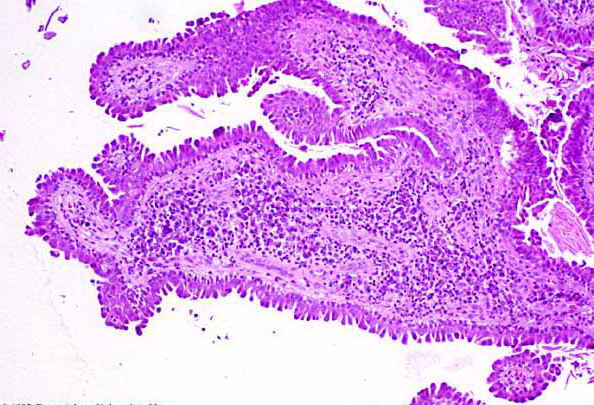

Syringocystadenoma = غدوم كيسي عرقي